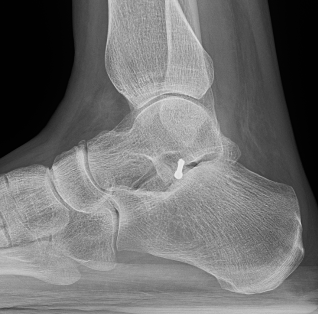

X-ray

Best seen on mortise view

| Non operative | Non operative | ORIF |

ORIF if able Excise fragments to prevent subtalar OA |

Operative Management

Indications

Large / displaced fragments

Intra-articular fracture with risk of subtalar OA

Options

1. ORIF - headless compression screw

2. Excision